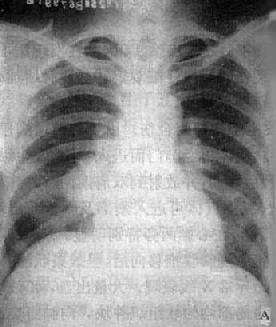

图3-1-24 右肺中心型肺癌伴肺门淋巴结转移

A.后前位 B.右侧位 C.侧位体层像

右肺门区可见圆形肿块影,边界清楚

体层摄影示肿块影边界不规则(→),

并见增大淋巴结向支气管突入